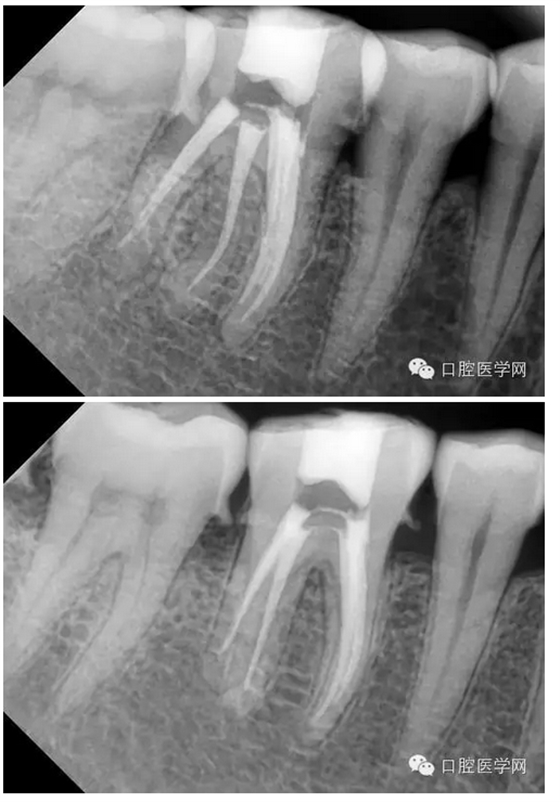

患者:男,44歲

主訴:右下后牙進(jìn)食痛2周,加重2天。

現(xiàn)病史:牙齒有洞,無不適,未處理,2周前開始進(jìn)食痛,口服消炎藥,好轉(zhuǎn),2天前晚上劇烈疼痛,今來看診。

檢查:#46牙頰側(cè)小洞,探(++),叩(-),冷熱(+++),咬頜正常,牙齦未見不適,未見其它不適。

診斷:#46牙髓炎

治療計(jì)劃:#46根管治療+冠修復(fù)保護(hù)。